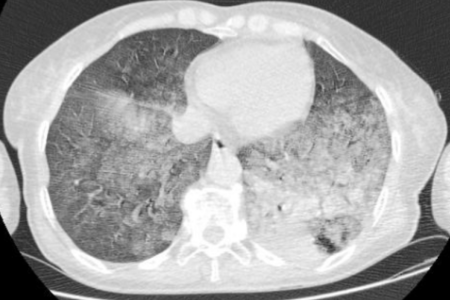

2024-5-2胸部CT影像

6月19日,患者来到了一家省级三甲医院,胸部CT显示她的双肺有大片状感染性病变,尤其是左肺下叶。肺功能检查结果显示,通气功能中重度受限,弥散功能严重下降。从一开始只是在活动后气短,现在却坐着都感到严重气短。

半年前患者无明显诱因出现咳嗽、咳痰,咳少量白痰,不易咳出,伴活动后胸闷气短,无咯血胸痛,无发热,无心悸头晕,无周身痛,曾于当地卫生院就诊,考虑“肺炎”,予以“阿莫西林”抗感染、止咳化痰等治疗后效果不佳,1月前感咳嗽、咳白色粘痰,痰量较前增多,呈拉丝状,感气短较前加重,休息时即感气短、呼吸困难、乏力,无发热、盗汗,无胸痛、咯血,无心悸头晕,于区人民医院就诊,查胸部CT提示双肺炎性改变。NGS提示烟曲霉,序列数13;肺孢子菌,序列数:79,予以“莫西沙星”抗感染、止咳化痰等治疗后症状未见明显好转。